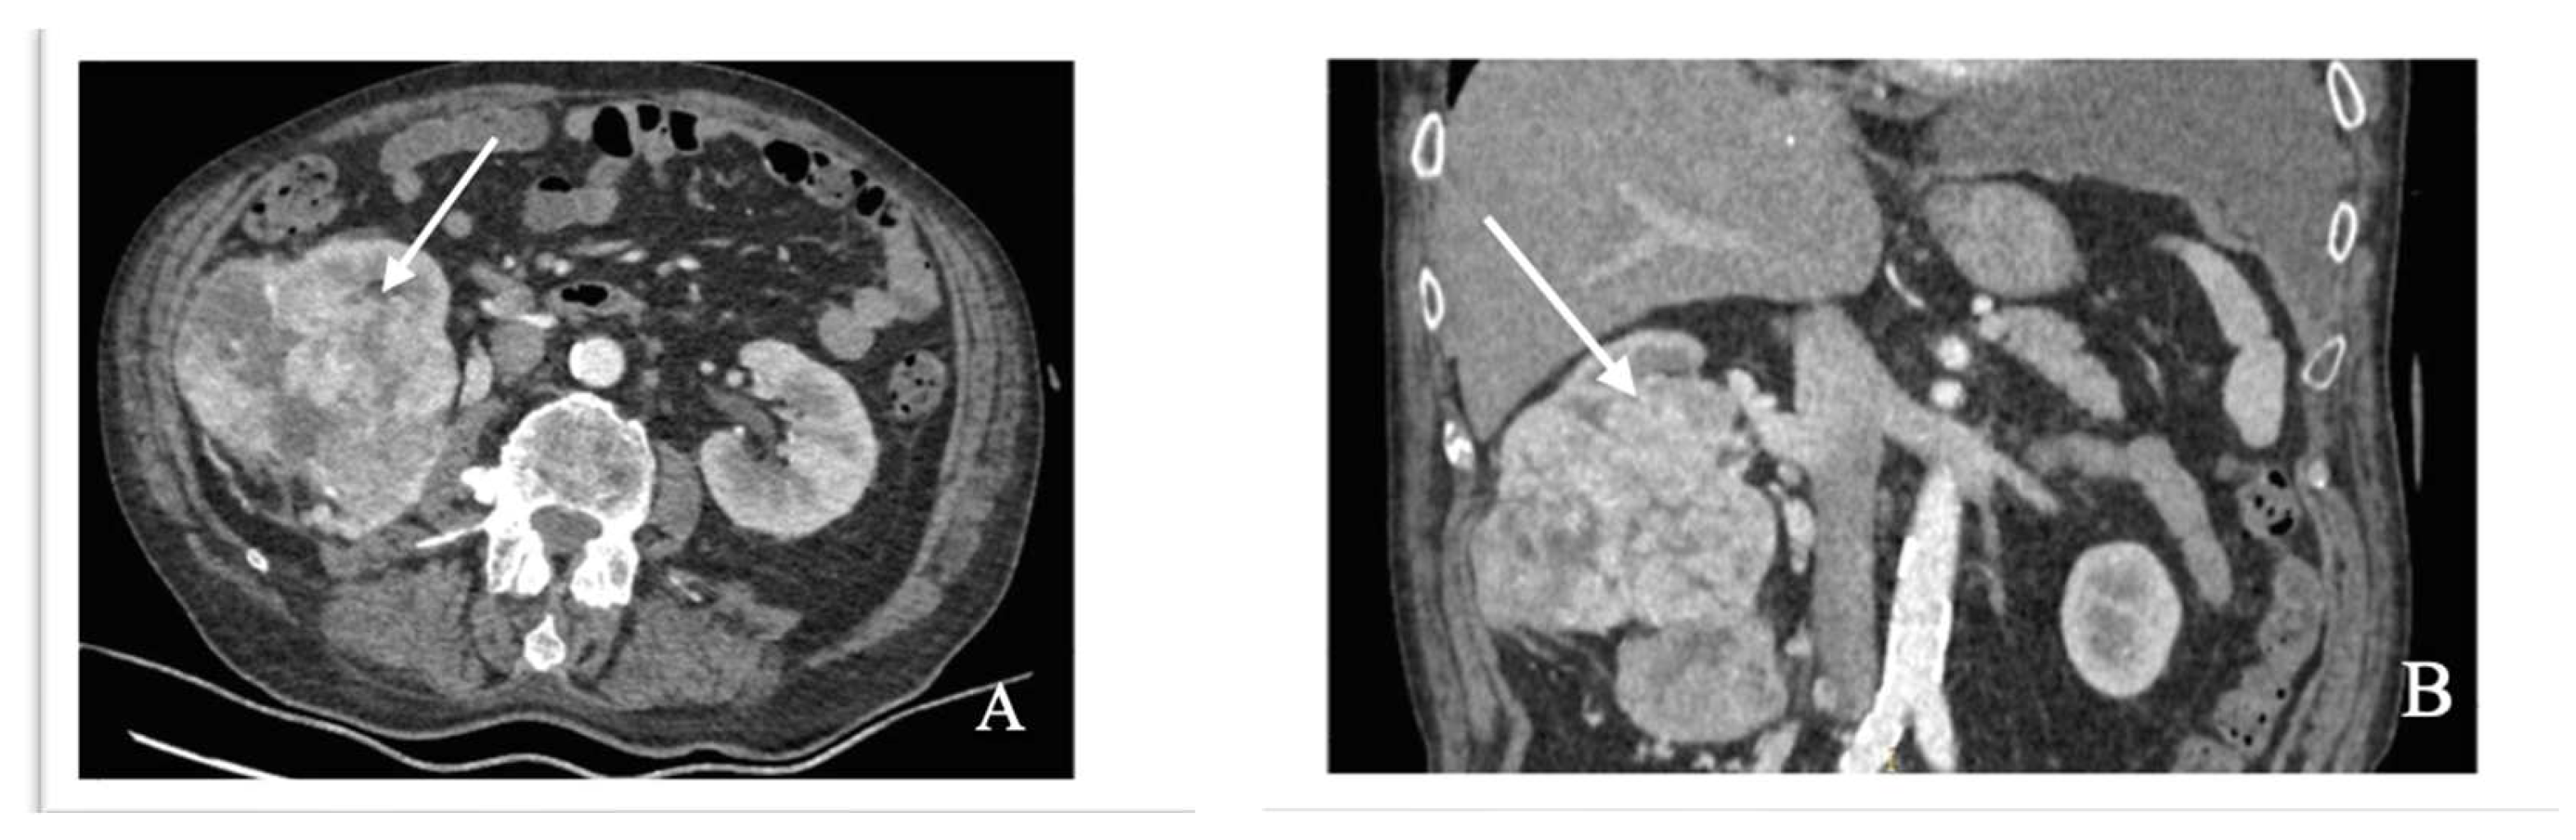

4.3. Case Report: Tumor-to-Tumor Metastasis to a RCC as the Initial Presentation of a Lung Adenocarcinoma